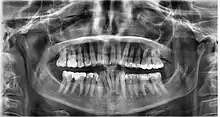

Dental